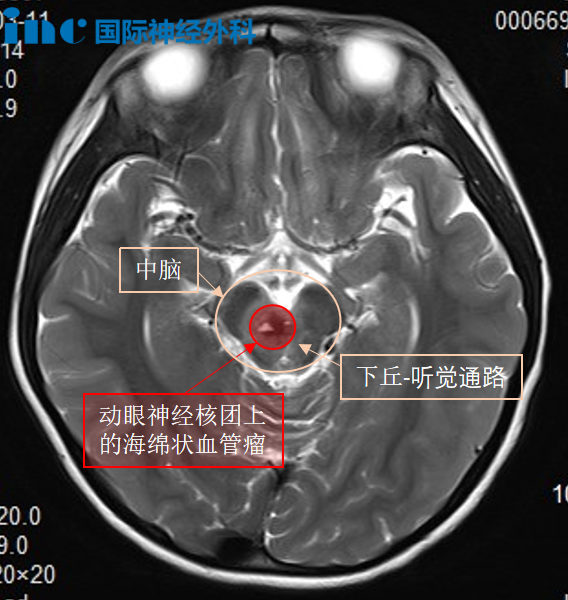

然而,手术困难远不止于此。除果果年龄小、出血风险更难控制外,肿瘤位置也十分棘手。肿瘤位于脑干中脑偏右侧,且累及动眼神经核——动眼神经是支配眼肌运动的主要神经,仅2毫米粗细,却与肿瘤紧密粘连。如果手术中动眼神经核完全损伤,果果的单侧眼睛将不能活动,且永远无法睁开。